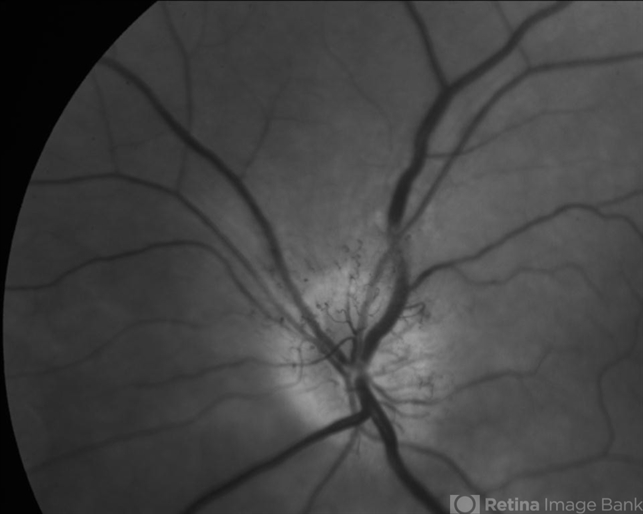

- anterior ischemic optic neuropathy

- Red Free photograph of acute AION